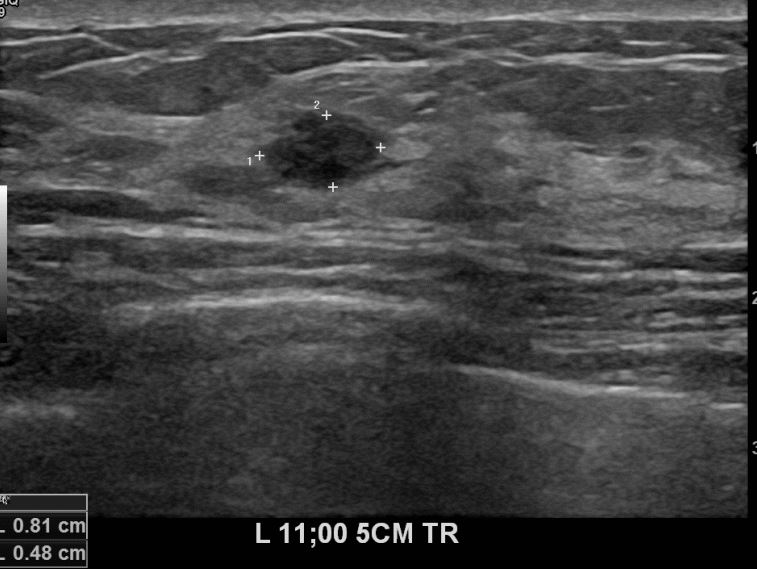

아산유외과 개원후 637번째 유방암진단

상기환자 외부검사상 이상소견으로 내원하신 40대여성으로 좌측 유방의 의심스러혹

조직검사시행해 유방암 진단되었읍니다